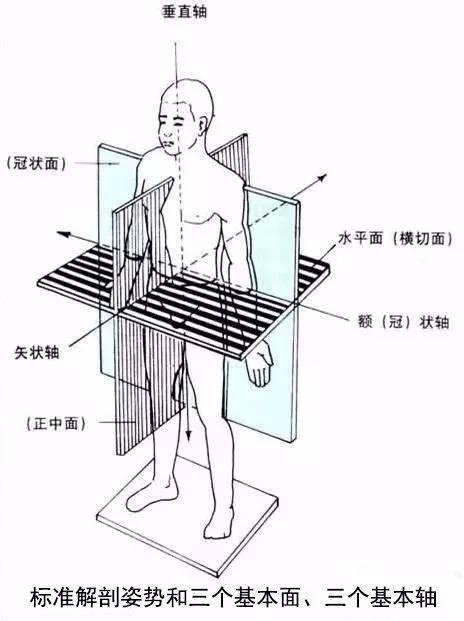

矢状面、冠状面、水平面が分からない? これで完全理解!! 身体の方向をあらわす3つの基準面 矢状面、冠状面、水平面 、本当に理解している?ここって、結構間違えやすい部分だよね。 なので、今回は「矢状面 正中面 」「冠状面」「水平面」のそれぞれの覚え方を。

身体の方向をあらわす3つの基準面 矢状面 正中面 、冠状面、水平面 のイラスト🎨 フリー素材 看護roo! カンゴルー。

矢状面、冠状面、水平面が分からない? これで完全理解!! 身体の方向をあらわす3つの基準面 矢状面、冠状面、水平面 、本当に理解している?ここって、結構間違えやすい部分だよね。 なので、今回は「矢状面 正中面 」「冠状面」「水平面」のそれぞれの覚え方を。

身体の方向をあらわす3つの基準面 矢状面 正中面 、冠状面、水平面 のイラスト🎨 フリー素材 看護roo! カンゴルー。

人体の基準面で矢状面 と 冠状面 がごっちゃになる人へ。 このイラストのイメージがあると記憶に残ります。

矢状面、冠状面、水平面が分からない? これで完全理解!! 身体の方向をあらわす3つの基準面 矢状面、冠状面、水平面 、本当に理解している?ここって、結構間違えやすい部分だよね。 なので、今回は「矢状面 正中面 」「冠状面」「水平面」のそれぞれの覚え方を。

矢状面、冠状面、水平面が分からない? これで完全理解!! 身体の方向をあらわす3つの基準面 矢状面、冠状面、水平面 、本当に理解している?ここって、結構間違えやすい部分だよね。 なので、今回は「矢状面 正中面 」「冠状面」「水平面」のそれぞれの覚え方を。

horizontal sagittal and coronal planes水平面,矢状面,冠状面 _sigittal coronalhorizontal之间的区别-CSDN博客。

人体の3つの基準面 矢状面・冠状面・水平面.組織細胞ゴロー .体のしくみ医療系学生の勉強垢看護学生の勉強垢鍼灸科理学療法学科作業療法士の勉強垢解剖生理学ノート解剖学講座生理学ノート国試過去問柔整科歯科衛生学生ナース。

强强的个人技术博客-医学中水平位、冠状位、矢状位这三个位置的概念分别是什么。

分清frontal plane 额状面 、coronal plane 冠状面 、transverse plane 横断面 、sagittalplane 矢状面 -CSDN博客。

关于医学影像中的轴位面 横断面 、冠状面、矢状面的解释_ct轴位和冠状位的区别-CSDN博客。

医学图像的三个主要平面:矢状面、冠状面、横断面_冠状面和矢状面示意图-CSDN博客。